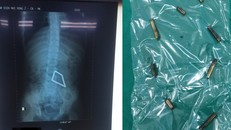

Bé trai nhập viện sau 2 ngày đau bụng. Qua nội soi, bác sĩ ghi nhận bé bị thủng ruột nhiều nơi do 8 thanh nam châm ở các quai ruột khác nhau hít lại với nhau, tì đè lên thành ruột.